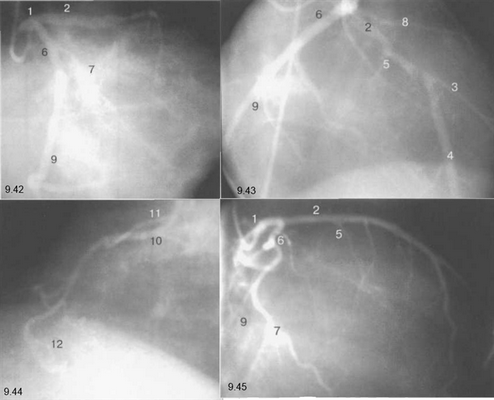

Здесь и на рис. 9.38—9.46:

1 — левая коронарная артерия; 2 — проксимальная треть передней нисходящей артерии; 3 — первая диагональная ветвь передней нисходящей артерии; 4 — дистальная часть передней нисходящей артерии; 5 — септальная ветвь передней нисходящей артерии; 6 — проксимальная часть огибающей артерии; 7 — первая маргинальная ветвь огибающей артерии; 8 — промежуточная артерия; 9 — дистальная часть огибающей артерии; 10 — проксимальная часть правой коронарной артерии; 11 — ветвь синусного узла правой коронарной артерии; 12 — ветвь острого края правой коронарной артерии; 13 — бифуркация правой коронарной артерии; 14 — правая левожелудочковая ветвь правой коронарной артерии; 15 — задняя нисходящая ветвь правой коронарной артерии.

На рис. 9.37—9.41 изображены левая и правая коронарные артерии и их ветви при равномерном типе коронарного кровообращения в обычной последовательности проекций.

На следующих рисунках представлены два типа коронарного кровообращения — правый и левый и характеризующиеся неравномерным развитием правой коронарной и огибающей (ветвь левой коронарной артерии) артерий. При левом типе отмечается выраженная периферия огибающей артерии при значительной гипоплазии правой коронарной артерии. При правом типе чаще всего хорошо развита маргинальная ветвь и гипоплазирована основная ветвь огибающей артерии. Периферия правой коронарной и, в особенности, правая левожелудочковая ветвь значительно выражены и превосходят огибающую по размерам зоны кровоснабжения.

Рис. 9.42-9.44 — левый тип коронарного кровообращения.

Рис. 9.45 и 9.46 — правый тип коронарного кровообращения.

Рис. 9.42. Левая коронарная артерия. Правая косая проекция.

Рис. 9.43. Левая коронарная артерия. Проекция «паук».

Рис. 9.44. Правая коронарная артерия. Левая косая проекция.

Рис. 9.45. Левая коронарная артерия в правой косой проекции.

Рис. 9.46. Правая коронарная артерия в переднезадней проекции.